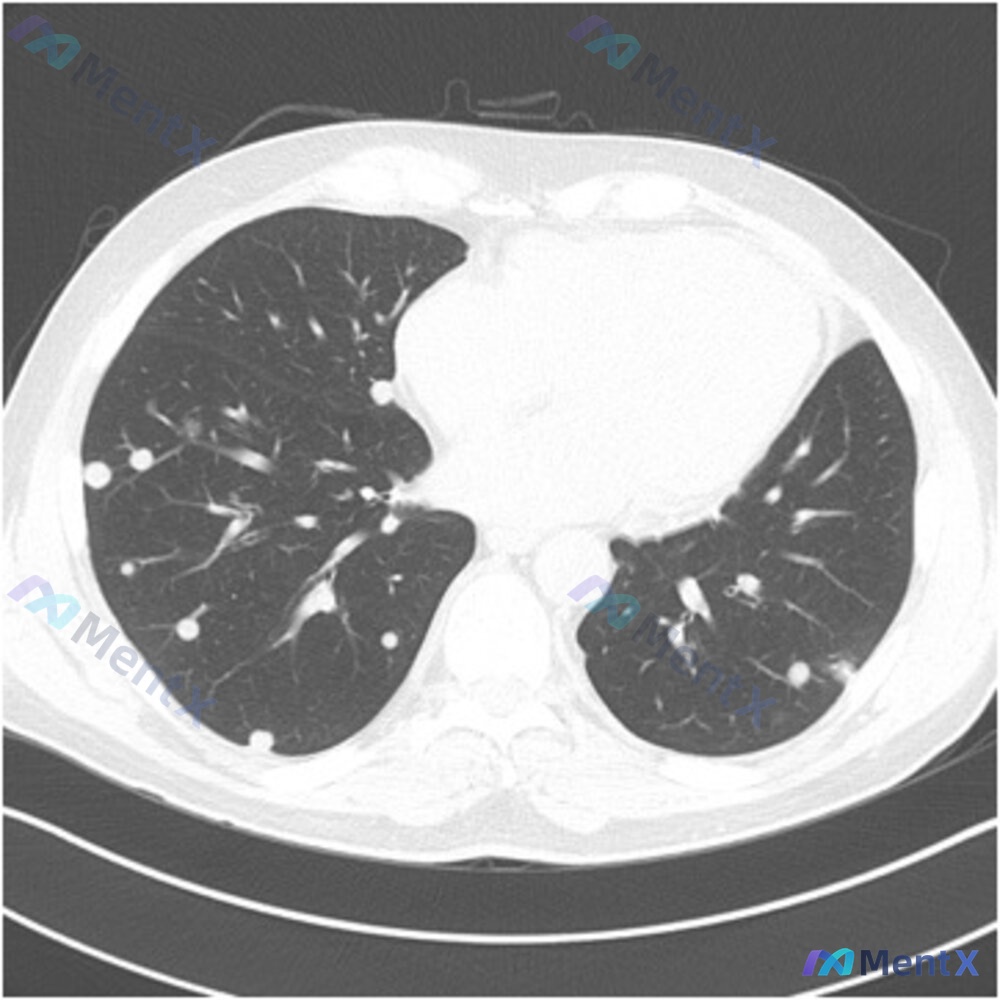

整理了一个非常有意思的病例,看到影像初看很容易被带偏,最后病理和旅行史才是关键。 病例基本情况 - 患者:60岁男性传教士 - 主诉:干咳1个月,从尼加拉瓜旅行回来5天后开始出现症状 - 症状:除干咳、发热、发冷、盗汗、肌痛、轻度呼吸急促 - 暴露史:否认接触野生动物/新性接触,但提到住在一家正在装...